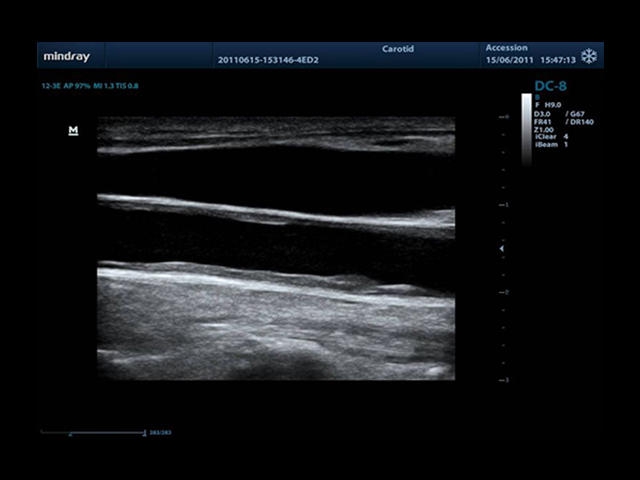

• Auto IMT Package - измерения и анализ толщины комплекса интима-медиа (КИМ) сонной артерии.

Сверхширокополосная нелинейная обработка изображений снижает визуальные шумы на 30% по сравнению с другими системами. Технология iClear позволяет устранить зернистость изображения, а iBeam (технология пространственного компаундинга) обеспечивает высокое качество сканирования органов и тканей под различными углами.